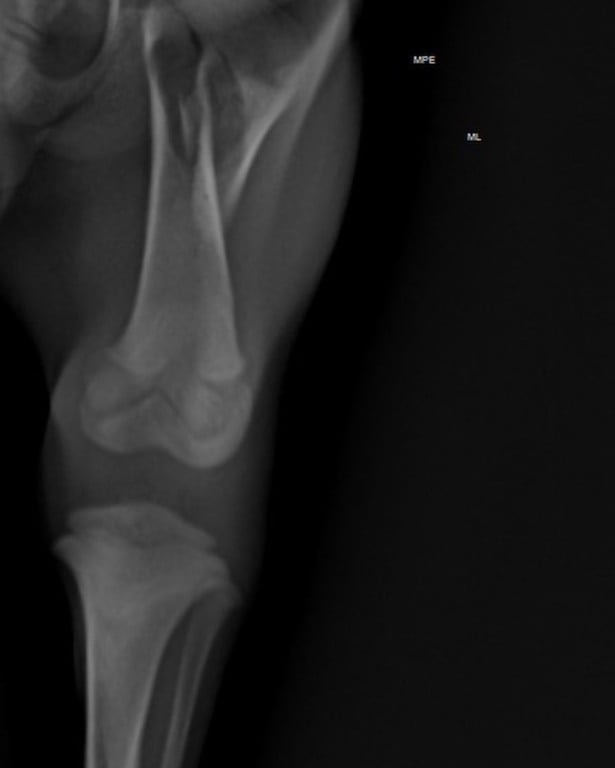

De acordo com a Associação Abrigo Temporário de Animais Necessitados (AATAN) de Sorocaba, Enrico sofreu uma fratura no fêmur por causa da queda. Se a cirurgia não for realizada a tempo, o filhote pode ter os movimentos das patas comprometidos.